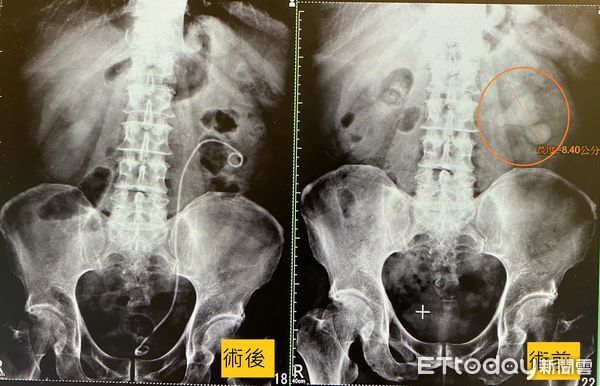

▲因疫情延誤,男子中斷追蹤,時間一長結石已經在體內長成8.4公分大。(圖/長安醫院提供)

南投一名65歲張先生長期有腎結石的狀況,也曾在外院做過體外震波碎石術,但依舊沒排乾淨。因疫情而中斷定期檢查,最近發現如果跑步或走路走久,就會有血尿的狀況,就醫檢查赫見結石已經長成巨無霸般的鹿角造型,且有8.4公分大,透過軟式輸尿管鏡碎石術,把這顆巨無霸腎結石處理乾淨。醫師也警告,再拖下去,恐面臨洗腎情況。